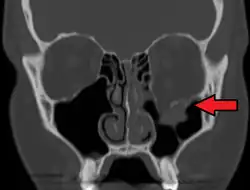

La radiografía, proyecta imágenes de los tejidos usando los rayos x, se utiliza para descartar fracturas faciales.[18] La angiografía (radiografías tomadas del interior de los vasos sanguíneos) se puede utilizar para localizar el origen del sangrado.[19] Sin embargo, la totalidad de los huesos y tejidos de la cara pueden hacer que sea difícil interpretar las radiografías simples, la tomografía axial computarizada es mejor para detectar fracturas y el examen de los tejidos blandos, y con frecuencia es necesaria para determinar si la cirugía es necesaria, pero es más cara y difícil de obtener.[3] La tomografía axial computarizada generalmente se la considera más definitiva y mejor para detectar las lesiones en la cara que rayos x.[1] La tomografía axial computarizada es especialmente probable que se utilice en personas con lesiones múltiples que necesitan la tomografía axial computarizada para evaluar otras lesiones de cualquier manera.[20]